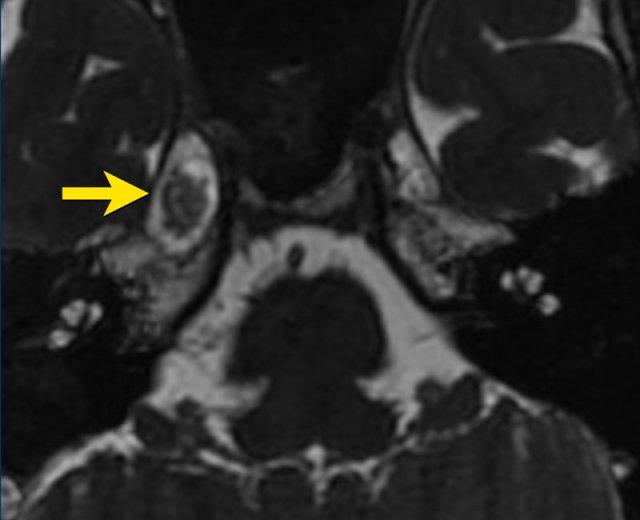

Bệnh nhân nữ 45 tuổi với tiền sử đau vùng hàm dưới bên phải, đã được giảm đau sau khi nhổ nhiều răng.

Tuy nhiên, trong vòng một tháng gần đây, bệnh nhân lại xuất hiện cơn đau tương tự. Cơn đau có tính chất sắc bén, lan từ vùng cằm, dọc theo bên phải của mặt lên đến đầu. Cơn đau được khởi phát khi nói chuyện, ăn uống và chạm vào bên phải của mặt.

Hình ảnh

Chuỗi xung 3D FIESTA cho thấy một tổn thương tại hang Meckel, tăng tín hiệu trên DWI, giảm tín hiệu trên ADC (không hiển thị), lan rộng vào đoạn bể dịch não tủy.

Tổn thương này nghi ngờ là u bì thượng bì (epidermoid).